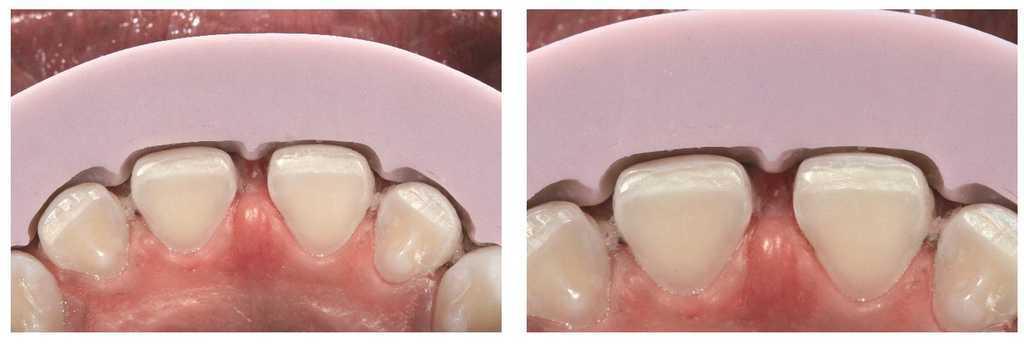

Figs. 9a a 9c. La situación 90 días después de la intervención quirúrgica y un blanqueamiento de dos semanas en casa. El recorrido gingival sigue la línea labial inferior y ya no se aprecia sonrisa gingival

Figs. 10a y 10b. El nuevo recorrido gingival.